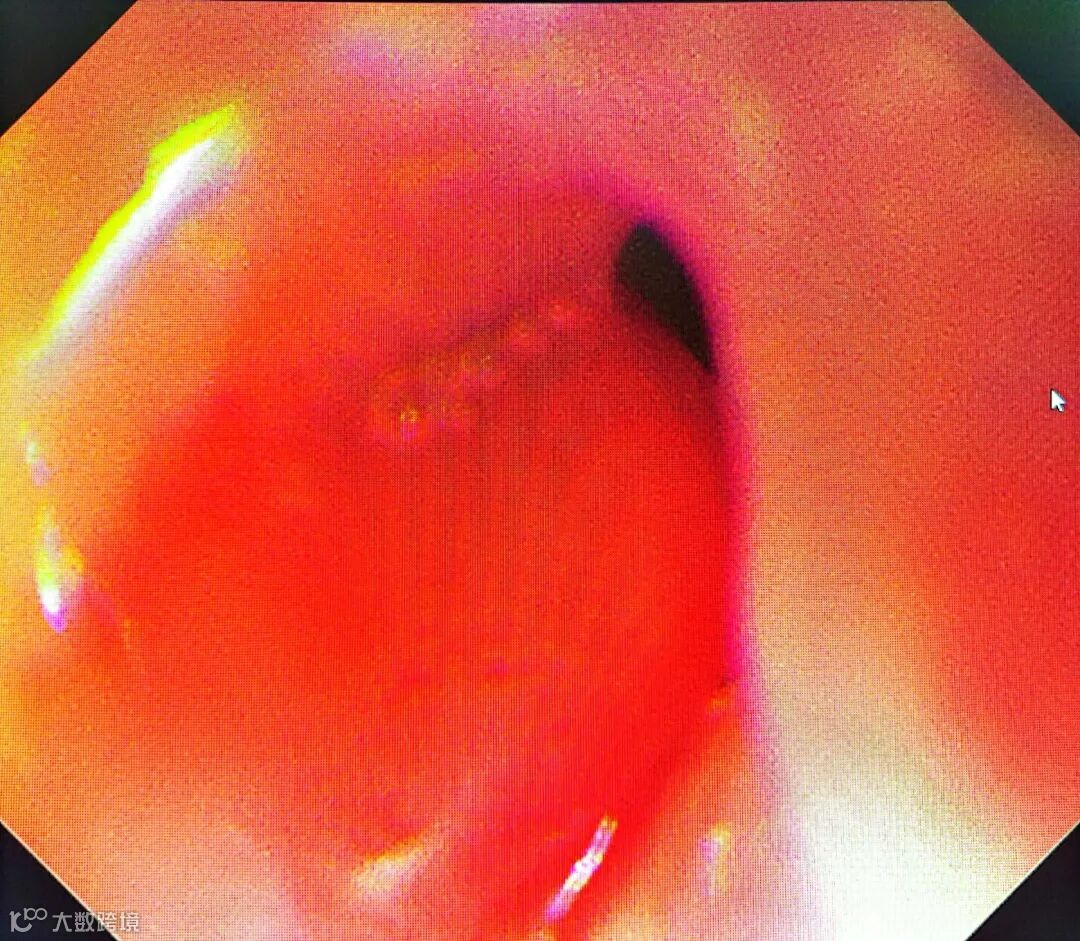

食管狭窄

球囊扩张术简单来说就是在食管内放进去一个小球,充气将食管扩开,然后再将球内的气体抽出,将球取出体外,达到扩张食管的目的。

这种方法操作简单、安全性高、恢复快、治疗成本低,可用于治疗食管、胃、十二指肠及结直肠的各种良性狭窄,例如各种情况引起的消化道炎症性狭窄、手术后的吻合口狭窄、贲门失驰缓症等,也可用于治疗部分恶性狭窄。

内镜下食管狭窄球囊扩张术

手术只用了不到20分钟

过程顺利

通过手术

王奶奶的食管吻合口

由0.4厘米扩张到了1.4厘米